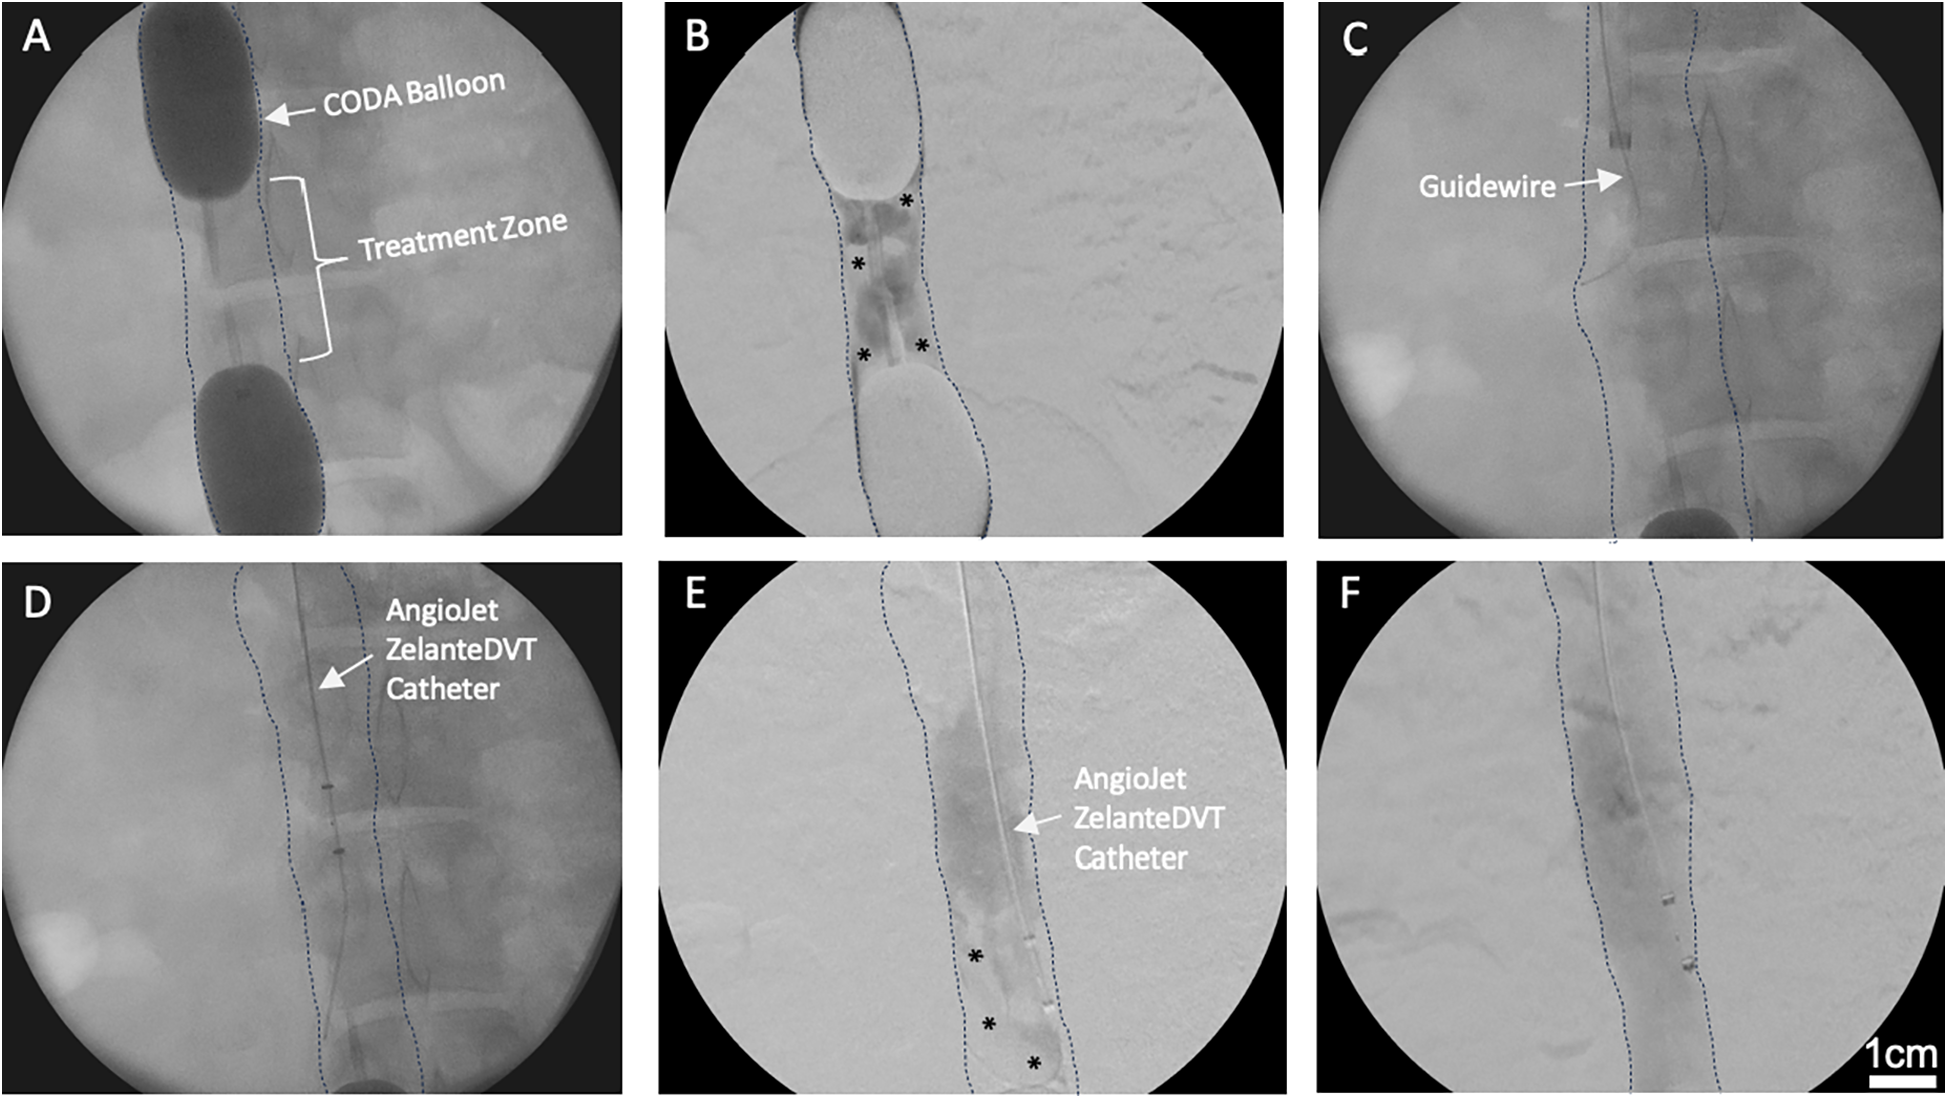

Figure 2

Venography of in vivo porcine acute DVT model and ART system. (A) Two CODA Balloon Catheters were inflated into IVC to create a treatment zone. (B) Thrombus (Asterisks) was developed within the treatment zone after 25% ethanol infusion. * indicates intraluminal thrombus. (C) Amplatz stiff guidewire was introduced into the treatment zone. (D) ART ZelanteDVT Catheter was introduced over the guidewire into the treatment zone. (E) Mechanical thrombectomy was initiated by activating the ART thrombectomy system. * indicates intraluminal thrombus. (F) Pharmacomechanical catheter-directed thrombolysis was initiated by injecting 50,000 IU 10 ml Streptokinase through ART Power Pulse, then ART console was activated.

Venography analysis

The average width and length of the sequestered venous segment in six pigs were 2.6 ± 0.6 and 5.5 ± 0.8 cm, respectively. Serial venograms in the sequestered segment demonstrated thrombus formation as early as 10 min post-ethanol infusion (PEI). Thrombus volume increased over time and reached 64.7% ± 9.7% maximal capacity thrombosis (MCT) at 30 min PEI. Overall, we observed that ART significantly decreased thrombus volume in all six pigs compared to baseline (64.7% ± 9.7% vs. 16.1% ± 10.5%; P = 0.02; Figures 2E,F). In addition, thrombus reduction percentage was similar between MT and PCDT groups (75% ± 18% vs. 77% ± 13; P = 0.93).